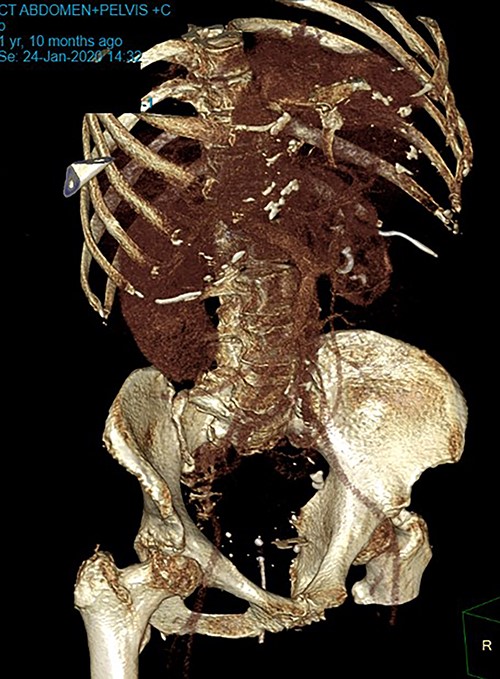

Patient SC is a 72-year-old lady who presented with urosepsis secondary to a left-sided distal ureteric renal stone. Her medical history includes ischemic heart disease, chronic pulmonary obstructive airway disease, type 2 diabetes mellitus, Parkinson’s disease and a previous open cholecystectomy. She was admitted to the intensive care unit and a left-sided nephrostomy tube was inserted. Initial CT imaging incidentally identified a ‘bread clip’-shaped FB in the distal jejeunum (Figs 1 and 2). There was no evidence of obstruction nor perforation. Abdominal X-rays failed to show the presence of a FB.

Secondly, as shown in the three cases, unless the BC is calcified, abdominal plain films are not a reliable method of tracking nor diagnosing BC ingestion [9–13]. CT is more sensitive, with a sensitivity rate of 67%, but is not consistently reliable on its own [6, 7]. Reconstructed 3D imaging is effective in identifying BCs. Most BCs are made of low-density polystyrene, a type of versatile solid plastic, which are not readily identified on plain film imaging [14, 15]. This non-degradable plastic means that it is usually only a matter of time before a patient develops a complication.